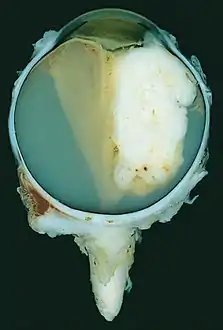

| A pathology specimen of a retinoblastoma tumor from an enucleated eye of a 3-year-old female | |

Morphology

Gross and microscopic appearances of retinoblastoma are identical in both hereditary and sporadic types. Macroscopically, viable tumor cells are found near blood vessels, while zones of necrosis are found in relatively avascular areas. Microscopically, both undifferentiated and differentiated elements may be present. Undifferentiated elements appear as collections of small, round cells with hyperchromatic nuclei; differentiated elements include Flexner-Wintersteiner rosettes, Homer Wright rosettes,[29] and fleurettes from photoreceptor differentiation.[30]

Large exophytic white tumor with foci of calcification producing total exudative retinal detachment